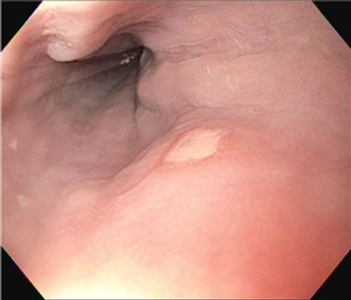

Comprehensive infectious workup was negative except for positive serum and CSF non-treponemal serology. Further testing of the previous right axillary LN specimen with IHC staining revealed Treponema pallidum and a diagnosis of neurosyphilis was confirmed and treatment with 14 days of IV PCN was commenced.

Figure 3: